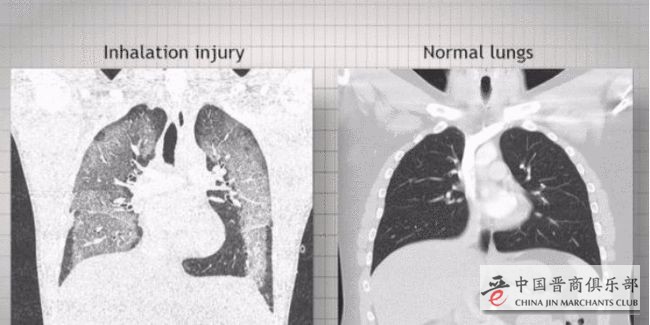

中国武汉的首例新冠病例于2019年12月8日发病,而美国在2019年的7月爆发了大规模不明原因的流感,由于美国每年的确会有大量的流感患者,所以当时各国均未重视美国的流感情况。然而美国的这一流感的症状却十分怪异,美国将其命名为“电子烟白肺病”。

在美国的马里兰州,“电子烟白肺病”的传播速度极快,2019年9月马里兰州报告病例数量已经翻了一倍。而这些“电子烟白肺病”也同样夺取了不少美国人的生命,但这些患者却有部分在死后被检测出患了新冠。赵立坚指出,这些患者的血清都需要被重新检测,不然无法得知美国初期疫情的真相,这些病例之中极有可能还存在大量新冠病例。